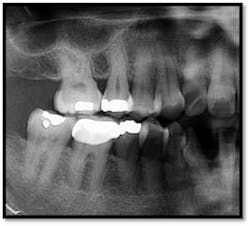

UL/LL reflected in a mirror and UL/LL radiograph

Treatment: FM Perioscopy completed in two, 2-hour sessions with local anesthetic and micro ultrasonics. No hand instruments are necessary during Perioscopy.